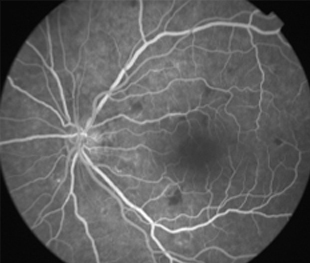

2 meses: disminución de manchas algodonosas y hemorragias con mejoría de circulación

- Angiografía: teñido arterial, escape capilar, más tardíamente, no perfusion arteriolar y venular con teñido de las paredes vasculares y dilatación venosa.